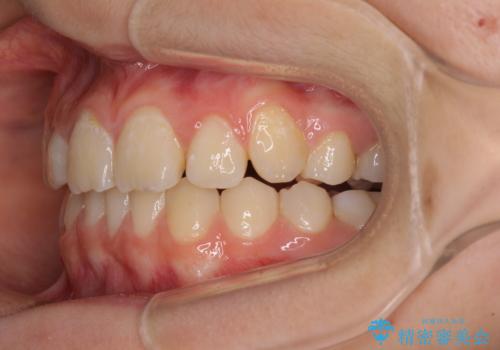

まずは補助装置を用いて八重歯を改善し、インビザラインにて歯列を整えましたが、当初の懸念が的中し、臼歯部の咬合を安定させることができませんでした。

海外留学の予定もあったため、後半は上下ワイヤー装置にて矯正治療を継続し、違和感なく咬合させることとなりました。